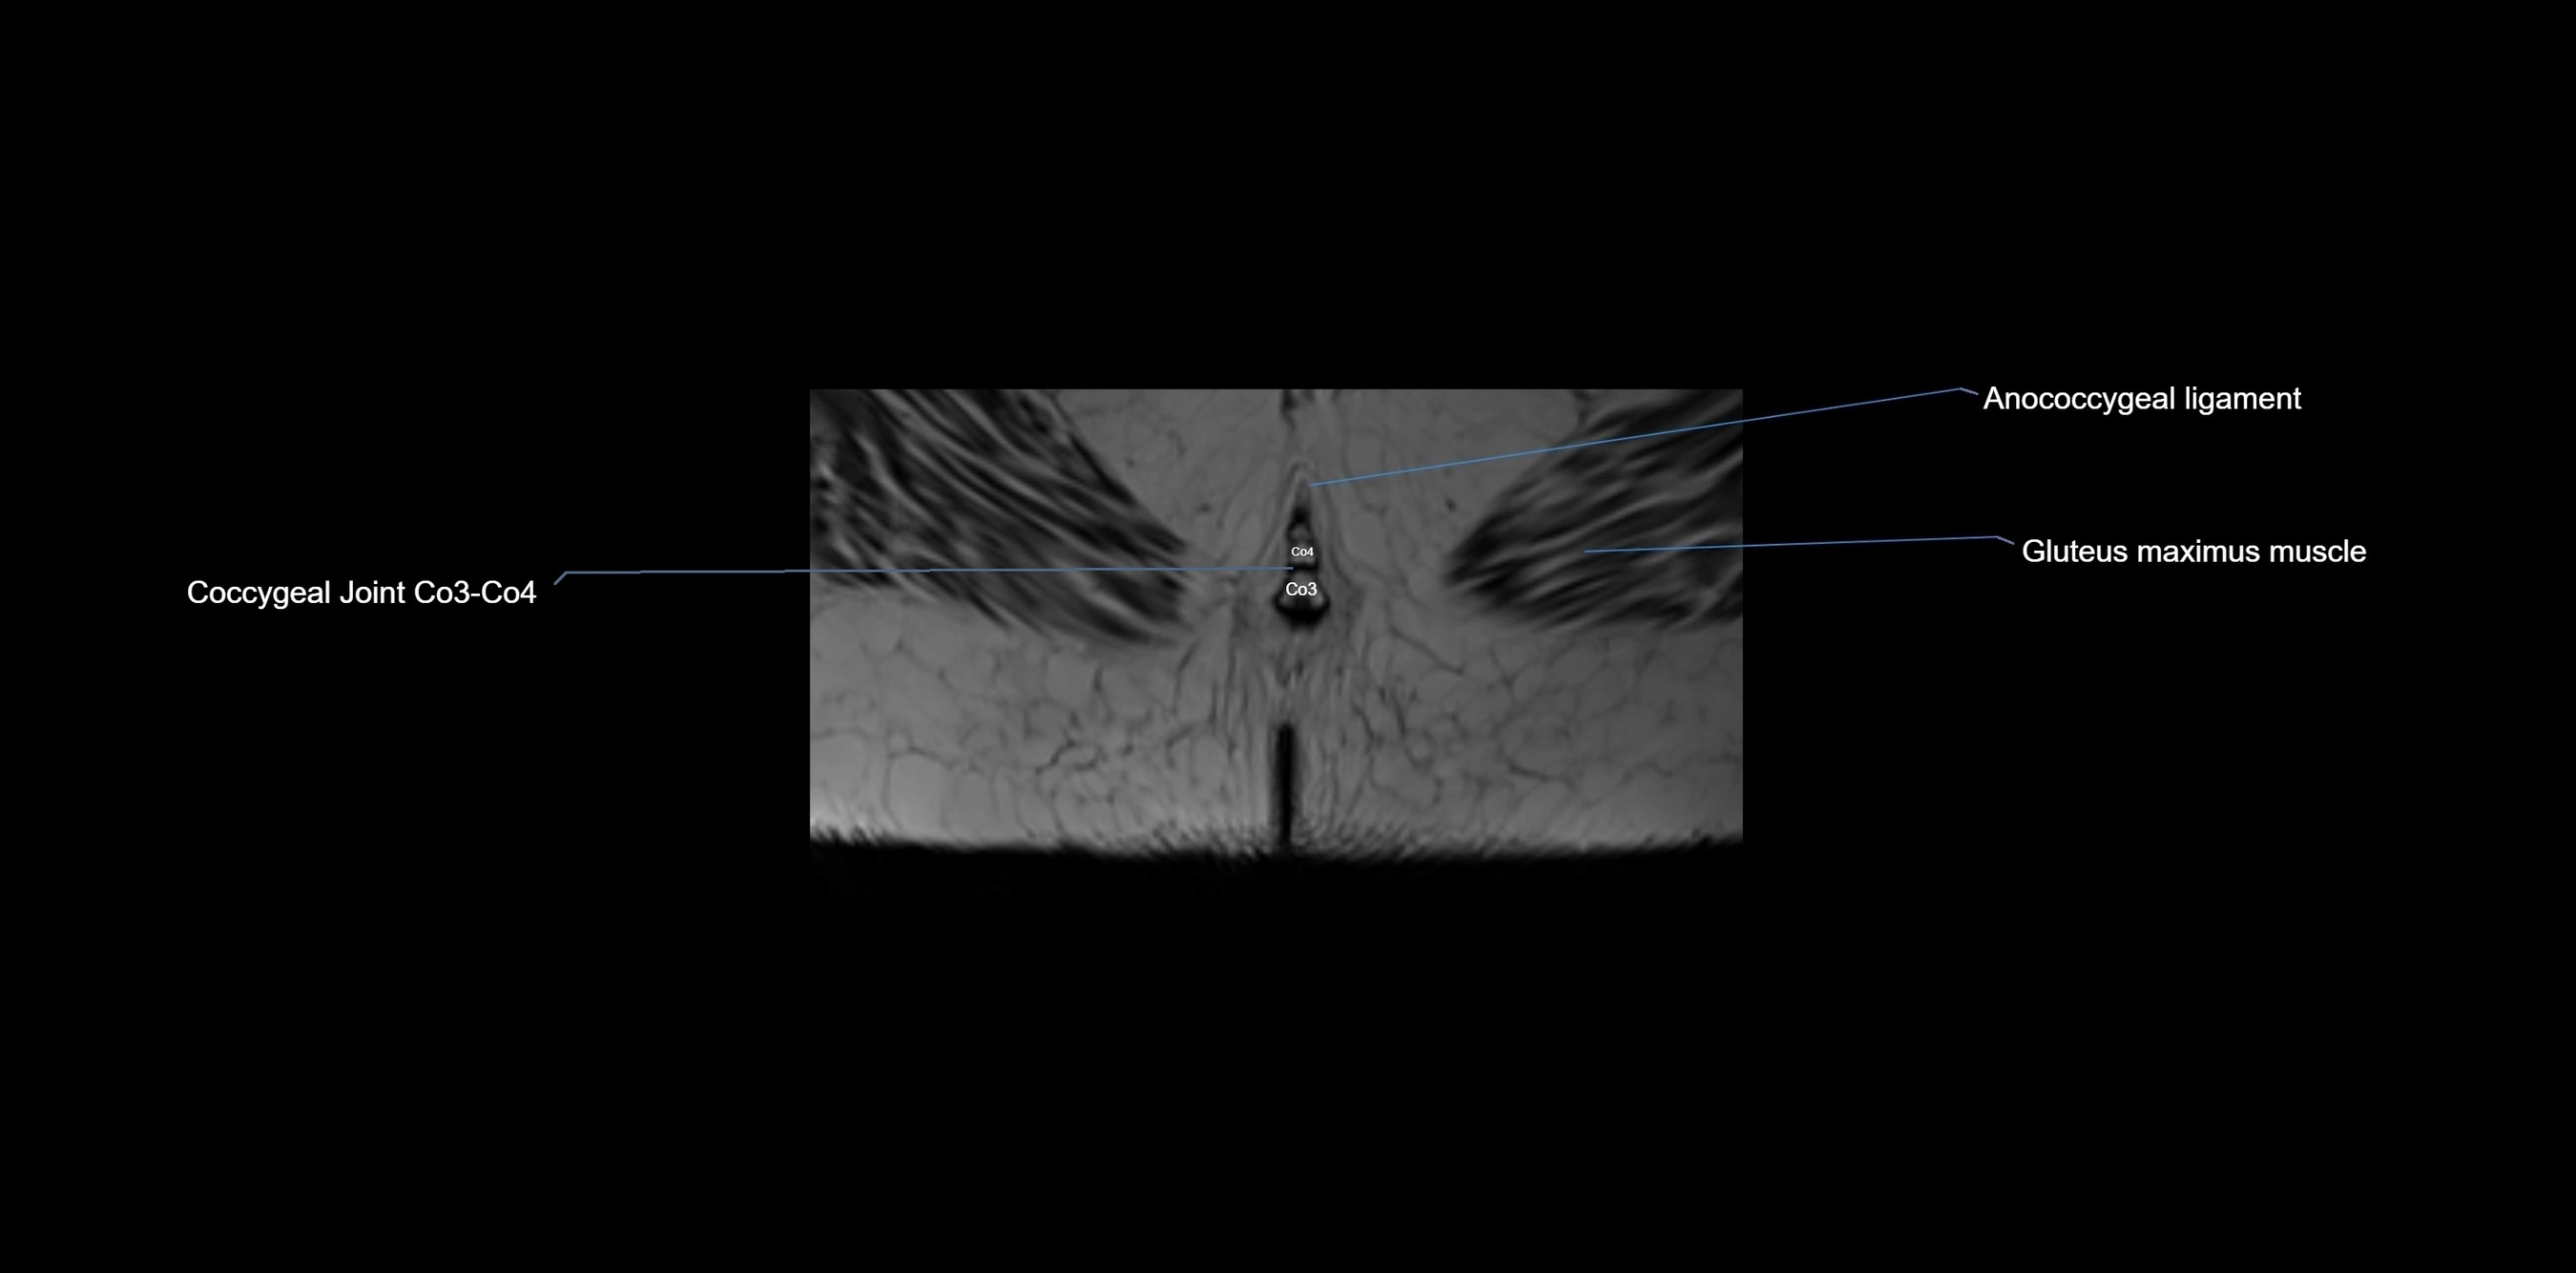

MRI image

image